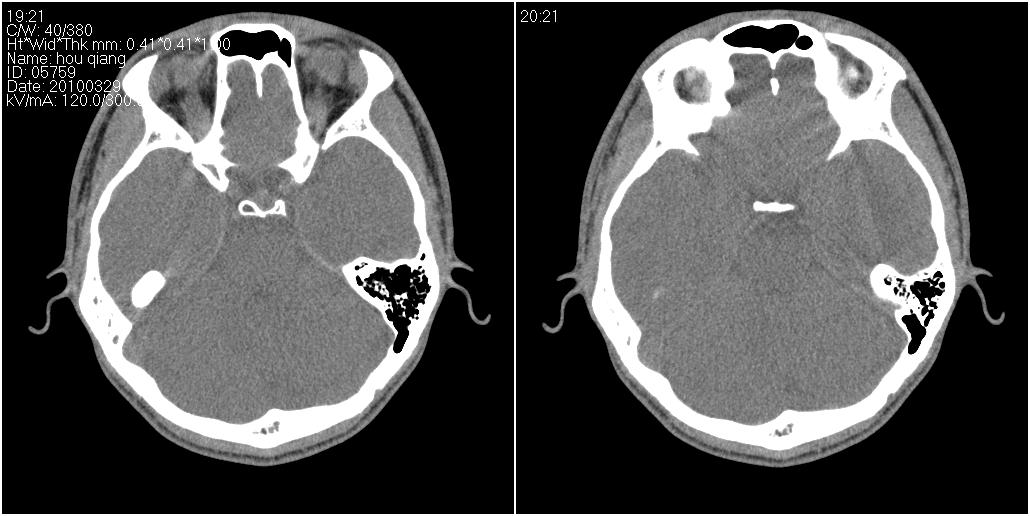

标题: CT25419:男性,18岁。右耳肿、痛5个多月。 [打印本页]

标题: CT25419:男性,18岁。右耳肿、痛5个多月。

右侧中耳乳突炎累及外耳道,鼻咽腺样体肥大。

1)右侧慢性中耳乳突炎并右侧中耳腔及外耳道肉芽肿或胆脂瘤形成。2)鼻咽腺样体肥大。